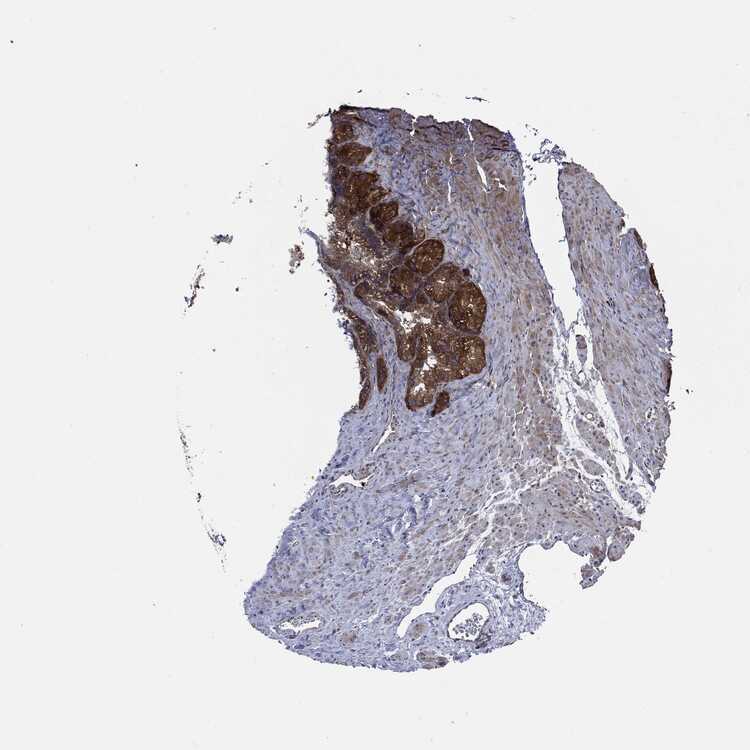

SEMINAL VESICLE - Antibody stainingi

Antibody staining in the annotated cell types in the current human tissue is reported as not detected, low, medium, or high, based on conventional immunohistochemistry profiling in selected tissues. This score is based on the combination of the staining intensity and fraction of stained cells.

Each image is clickable and will lead to virtual microscopy that enables deeper exploration of all samples and also displays staining intensity scores, fraction scores and subcellular localization as well as patient and tissue information for each sample.

Antibody HPA030419Antibody HPA030420Antibody HPA030422Antibody CAB025196Antibody CAB080286Antibody CAB080287

Glandular cells Not detectedNot detectedMediumMediumMediumMedium